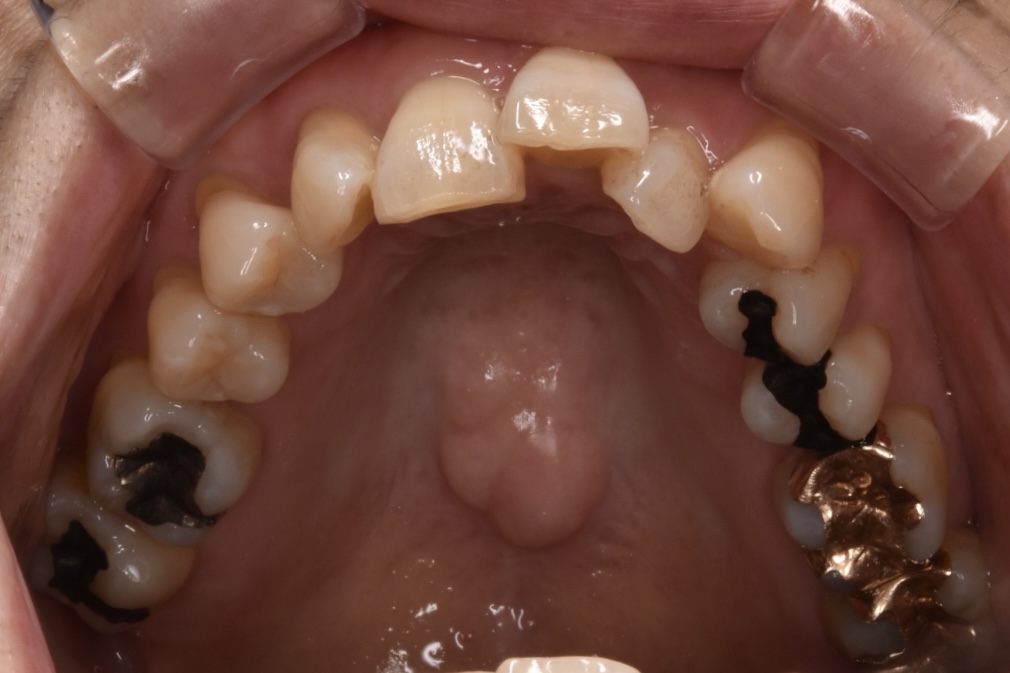

矯正前

前歯を中心に叢生(ガタガタ歯並び)がみられます。

矯正前の横顔や正面、咬合面の写真です。